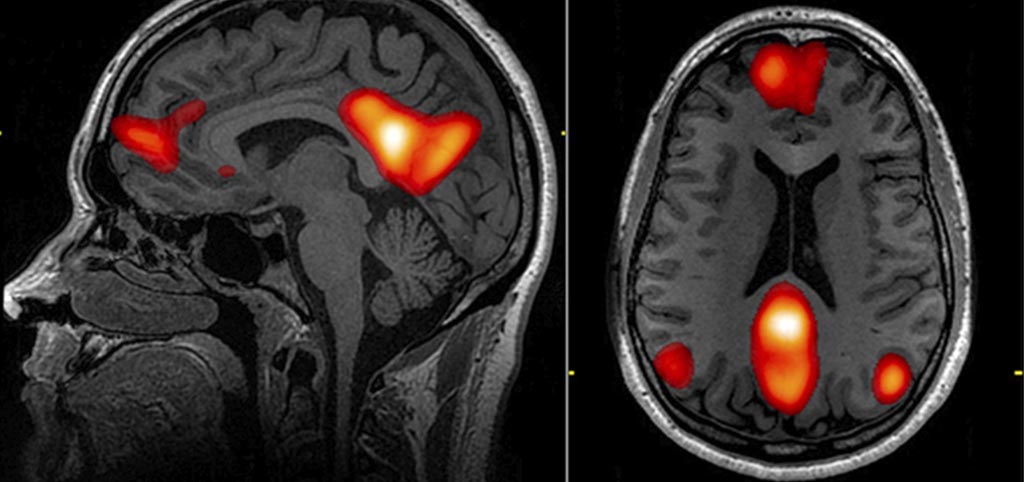

Analytical Strategies in Imaging Genetics

Assessment of potential risk factors for neurodevelopmental domains

Photo: John Graner, Neuroimaging Department, National Intrepid Center of Excellence, Walter Reed National Military Medical Center, 8901 Wisconsin Avenue, Bethesda, MD 20889, USA

Natalia Vilor, predoctoral researcher at ISGlobal, will defense her thesis "Analytical strategies in Imaging Genetics: Assessment of potential risk factors for neurodevelopmental domains". Free entrance.